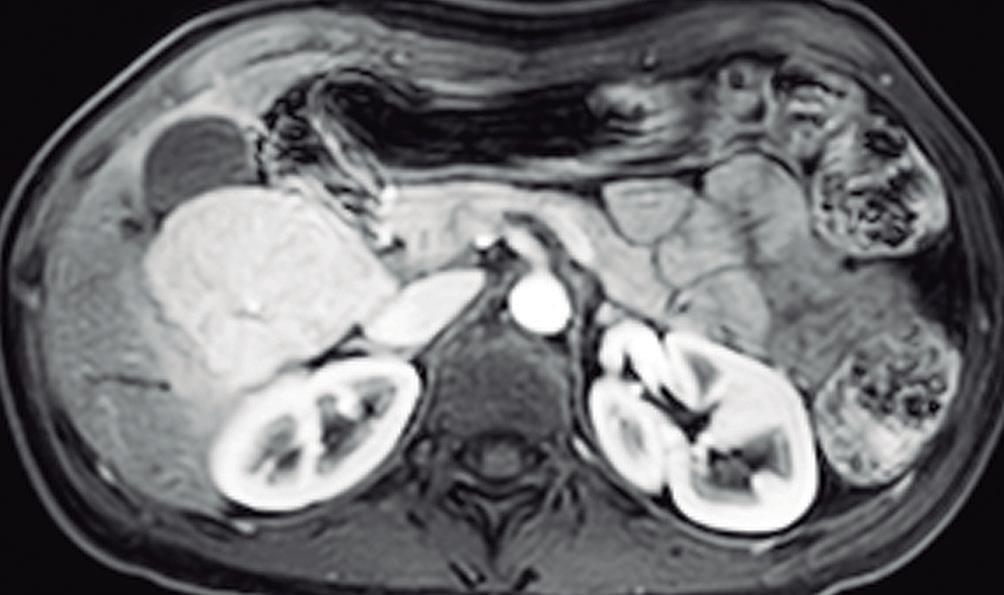

Este subtipo, el segundo en frecuencia, suele asociarse al uso de ACO y también en pacientes con adenomatosis y poliposis adenomatosa familiar. El HNF1α codifica un factor de transcripción clave para la diferenciación, y para el metabolismo y transporte de lípidos en los hepatocitos. Estas lesiones se caracterizan por su curso indolente con riesgo escaso o nulo de sangrado o de malignidad, y por la abundancia de lípidos en sus células.11 Esta última característica es la que permite en muchos casos hacer un diagnóstico confiable de este subtipo de adenoma. En la TCMC

suelen ser hipodensos debido al contenido lipídico. No obstante, la RM merced al empleo de la secuencia GRE T1 dual, permite reconocer en forma específica la presencia de lípidos intravóxel, manifestando una caída de la intensidad de señal en la imagen fuera de fase con respecto a la imagen en fase. Por otra parte, su refuerzo poscontraste es menos intenso que el de los otros subtipos de adenoma. La baja densidad en la TCMC y baja señal en imágenes T1 con supresión grasa puede llevar a la errónea interpretación de lavado en imágenes tardías y por ende, simular un CHC. Este subtipo de adenoma tampoco expresa transportadores OATP B1 y B3. (Figura 7)

A: Imagen ponderada en T2 con supresion grasa que muestra un nodulo hipointenso con respecto al parenquima con bordes netos. B: Imagen ponderada en T1 dual en fase que demuestra a la lesion con una señal levemente hiperintensa. C: Imagen ponderada en T1 dual fuera de fase muestra caida de la intensidad de señal en forma difusa de la lesion confirmando la presencia de grasa microscopica. D: Imagen ponderada en T1 poscontraste en fase arterial, la lesion presenta refuerzo mayor al parenquima pero de menor intensidad que el de otras lesiones hepatocelulares. E: Imagen ponderada en T1 poscontraste en fase venosa portal que demuestra hipointensidad difusa de la lesion. Si bien podria interpretarse este hallazgo como lavado, dicho comportamiento obedece a la supresion grasa inherente a esta secuencia y no a un lavado verdadero. F: Imagen ponderada en T1 obtenida en fase hepatobiliar que muestra a la lesion hipointensa sin captacion del contraste.

Lesiones benignas localizadas en el hígado desde la mirada de las imágenes Mariano Volpacchio Figura 7. Adenoma hepatocelular con inactivación AHC-HNF1α A B C D E F